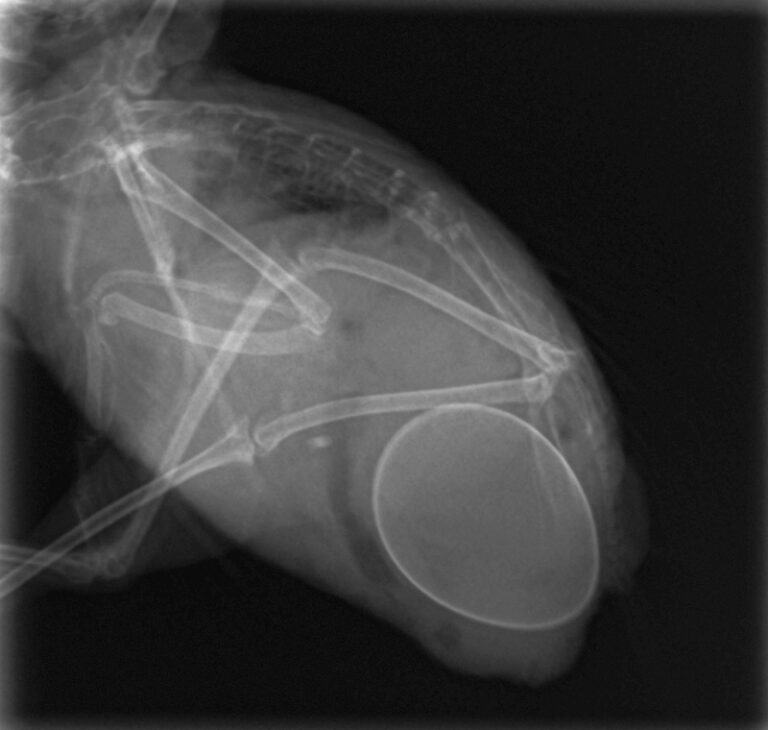

摘出後 糸で縫ってあります。眼球に接触しないように注意します。